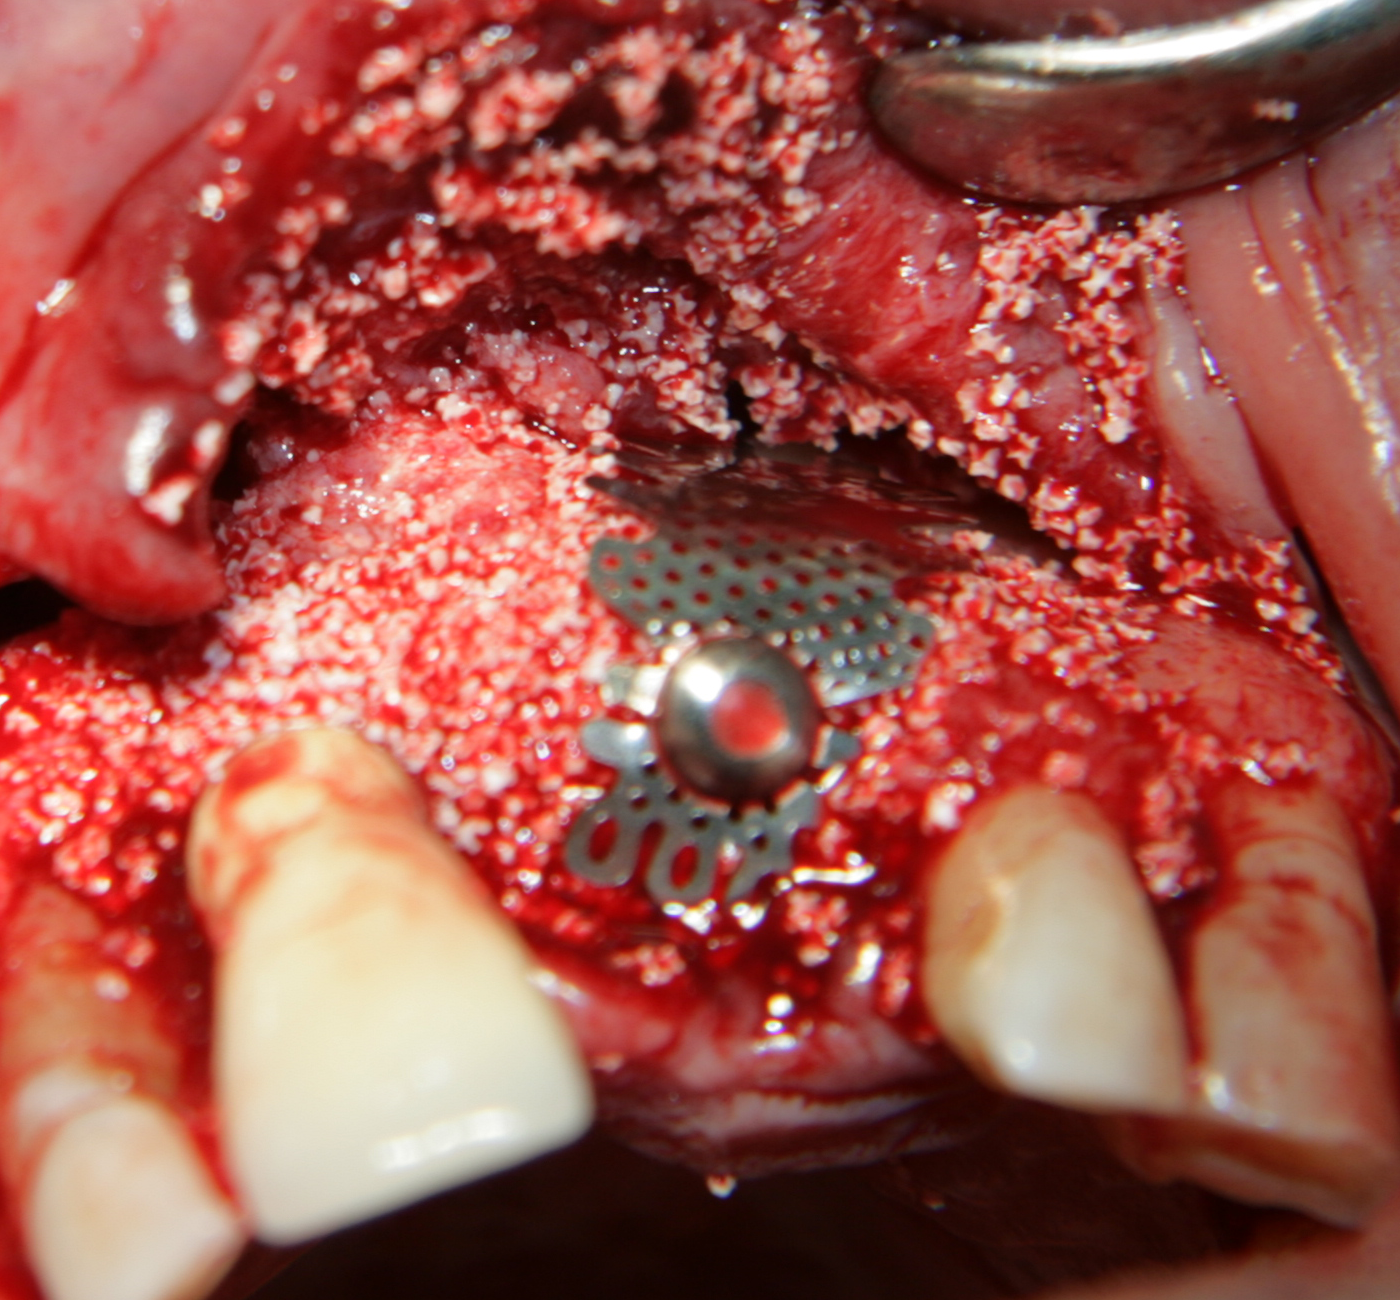

Титановите мембрани са твърди, ригидни приспособления, които се поставят в участъци с необходимост от увеличаване на костния обем - най-вече в областта на имплантологията, но също при радикуларни кисти и много рядко след екстракция на ретинирани мъдреци, при дефкетни фрактури, пострезекционни дефекти на челюстите, тежки остеомиелити и специфични възпаления на костта. Идеята на титановата мембрана е да предпази меките тъкани от колапс, поне за известен период от време, през който период под мембраната да започне костообразуване. През първите шест - осем месеца титановата мембрана оказва своя ефект, след което вече е безсмислено да остава в устата на пациента.

При операции с цел изграждане на допълнителн костна тъкан (костна пластика) винаги е добре да се перфорира кортикалната пластинка на костта. През тези перфорации излизат костни клетки, които постепенно прорастват в котозаместващия материал и синтезират нова костна тъкан. Перфорациите могат да се извършат с кръгло борче или с АСМ - фрезата на Neobiotech - Южна Корея.

Tent screw - винтове за

фиксиране на титановата мрежа

Около винтовете се поставя костозаместител, добре е да се размеси с

автогенна кост

Титанова мембрана